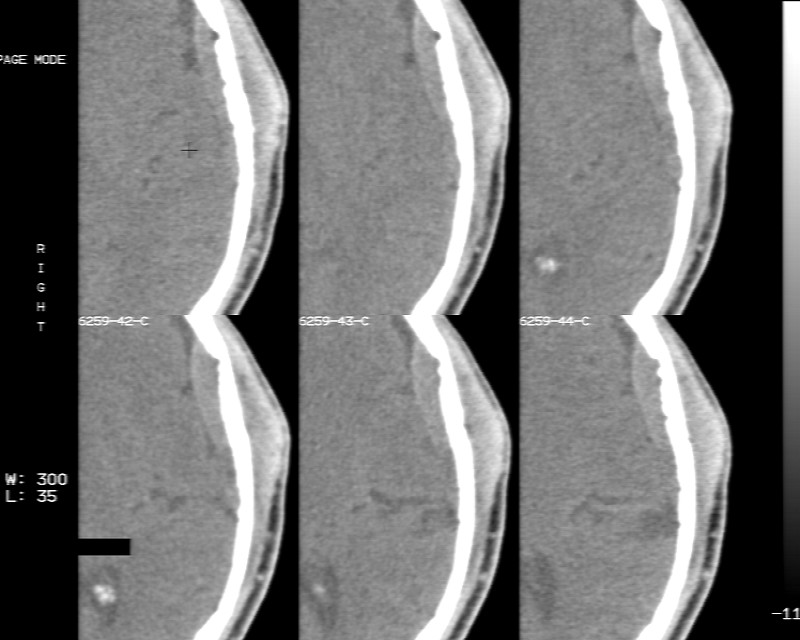

m70y, 2个月前发现左颞部有'包'隆起,近来自觉增大,无外伤无任何不适症状而就医,触诊包块质地较硬无移动无波动无皮温升高,胸片示右上肺陈旧结核....,ct扫描见左颞骨翼板局部内外骨板骨质破坏,似筛孔状,外板侧有骨膜线状增生,伴局部软组织丘状肿块,内板下梭形肿胀硬膜增厚翘起......颅内脑无异常.考虑骨良性病变 1.低度骨感染.   2.嗜酸性肉芽肿. 3.不排外骨结核...建议其穿刺活检,但患者失踪,追踪到结果定将公告.请大家分析.

左颞骨内板不光滑,密度减低,内板下可见新月形的软织密度影。脑实质轻度受压,外板外见膨胀形稍高密度影。考虑嗜酸性肉芽肿。建议增强扫描